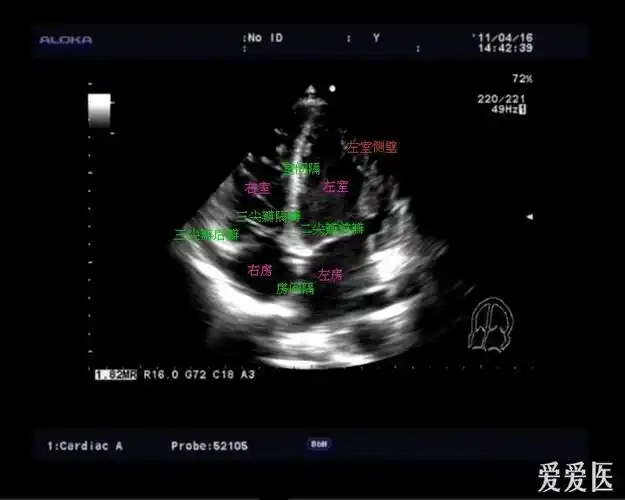

复习常用心脏切面 - 超声医学讨论版 - 爱爱医医学论坛